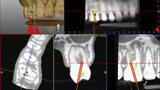

Fig. 1a: Static navigation stent used for endodontic access cavity preparations. The pre-planned stent does not allow for reorientation of the drill during the preparation. This can be consequential in accessing calcified, sclerosed canals. (Courtesy of Dr Paula Villa)

Fig. 1b: Three-dimensional stent printed for static navigation guidance to facilitate removal of an instrument in the periapex. Stents are cumbersome, bulky and restrictive in posterior regions. Once planned, the osteotomy path cannot be altered. (Courtesy of Dr Hugo Sousa Dias)